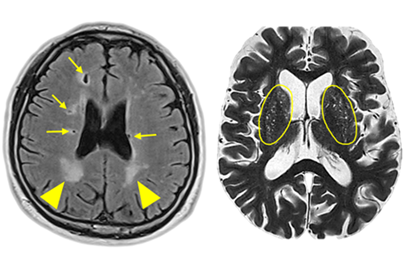

우선 뇌경색 초기증상이 보인다면 내원을 하기에 전문가와 상담을 진행하게 되겠고, 진척되는 뇌경색 검사형식으로는 뇌혈관 자기 공명영상, 공명영상 촬영술, 전산화 단층 촬영, 심장 초음파, 경동맥 초음파, 뇌혈관 초음파 등의 방법으로 환자의 현재 상태를 터득해서 치료가 진행되겠습니다.

이 질병을 진단하는 검사로는 몇 가지가 연속될 수 있다고 합니다. 뇌졸중에는 뇌출혈과 뇌경색이 실재하는데, 이 양쪽 모두는 양상이 다르며 무엇이냐에 따라서 치료 절차도 상이하기 때문에 뇌경색 검사방법으로 진단을 정확히 받아서 확인하는게 선행되어야 하고 귀중가운데 하나이라고 할 수 있고요.